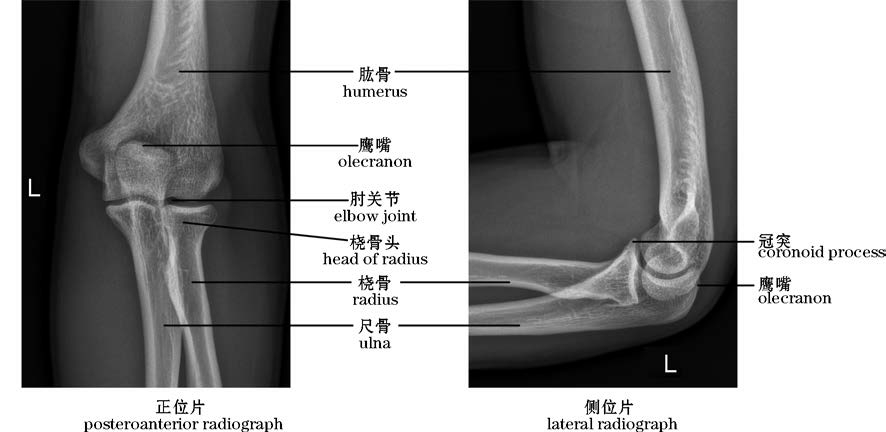

图2-27 肘关节X线片(右)

The elbow joint,X-rays(right)